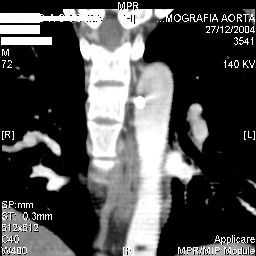

Коллеги,Шуруп в аорте? Как снимать конструкцию? Нужен ли контроль аорты? Читайте ниже.С уважением, д-р Архипов

Interesting case. Findings on CT: all four pedicle screws have been placed improperly inthat they miss the vertebral bodies. In addition, the screws on the left side are impingingon the decending thoracic aorta. What I do NOT know is the nature of the original injury, orwhether or not that injury has resolved. I would recommend removal of the hardware. I don'tthink it's a good idea to leave those screws where they are. If the original fracture ishealed, nothing else needs to be done.

dear Mark, all the details are not yet available but the patient is coming to see us foradvice. We probably will see him in the early new year. i thought that the 4th picture showedthe screw to enter the aorta? He is a victim of a motor vehicle crash and thoracic vertebralfracture which appears healed. He was posteriorly decompressed and this device inserted. asyou say there isno evidenece that any of the fixation enters the bodies via the pediclesistead they have passed thru and their end are no where near where they ought to be. If I amcorrect (I would prefer not to be) the aortic intima has been breached by the screw. When thetime comes to take the screw out I thought we should have control of the aorta.What do you think?

Mark Thank you. He is scheduled for a angio prior to transfer here. I keep going back to lookat that fourth image and although it is tough to believe the wall of the aorta seems toencompass the distal 1/2 of the screw. I have come to anticipate mal postion of screws thathave been inserted in hospitals that perhaps may not have the highest quality of equipment,including the human and radiological components. That having been said this case seems tosurpass the usual... one screw out of place or screwed into a disc etc. BTW I am notsuggesting that the screw was placed directly into the aorta but that moviment, pulse actionetc may have caused it to transgress the normal anatomical bounds without evident hemorrhage.

Подошли ангиограммы... Наслаждайтесь...